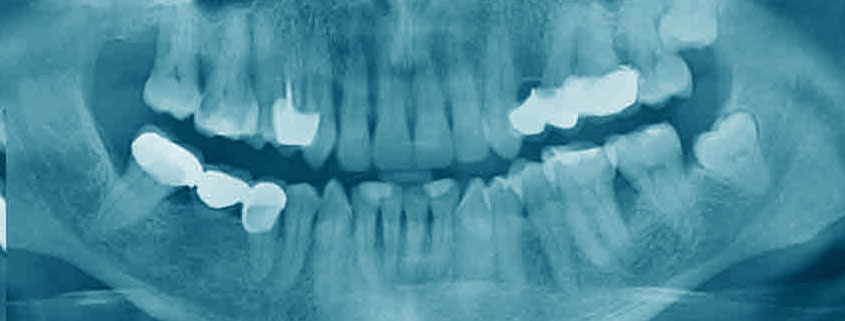

La radiologia digitale rappresenta una vera e propria svolta nell’ambito dell’imaging odontoiatrico. Rispetto alla tradizionale radiologia analogica, questa tecnologia offre numerosi vantaggi:

Le apparecchiature digitali di ultima generazione garantiscono immagini di altissima risoluzione, con una definizione ben superiore rispetto alle vecchie pellicole. Questo permette ai dentisti di ottenere una visione più dettagliata e accurata delle strutture dentali, facilitando così la diagnosi e la pianificazione dei trattamenti.

Accanto alla radiologia digitale, un’altra tecnica di imaging fondamentale in odontoiatria è la radiografia endorale. Questa tipologia di esame permette di ottenere immagini dettagliate di uno o più denti, concentrandosi sulla loro struttura interna.

La radiografia endorale, anche chiamata radiografia a mordente o radiografia periapicale, è un esame radiografico che consente di visualizzare in modo specifico l’anatomia di un singolo elemento dentale, dalla corona alla radice, incluso il tessuto gengivale circostante.

Per effettuare una radiografia endorale, il dentista posiziona una piccola lastrina fotosensibile all’interno della bocca del paziente, in corrispondenza del dente da esaminare. Il paziente viene invitato a mordere delicatamente sulla lastrina per mantenerla stabile durante l’esposizione ai raggi X. Grazie all’utilizzo di tecnologie digitali avanzate, l’immagine viene acquisita e visualizzata istantaneamente sul computer.